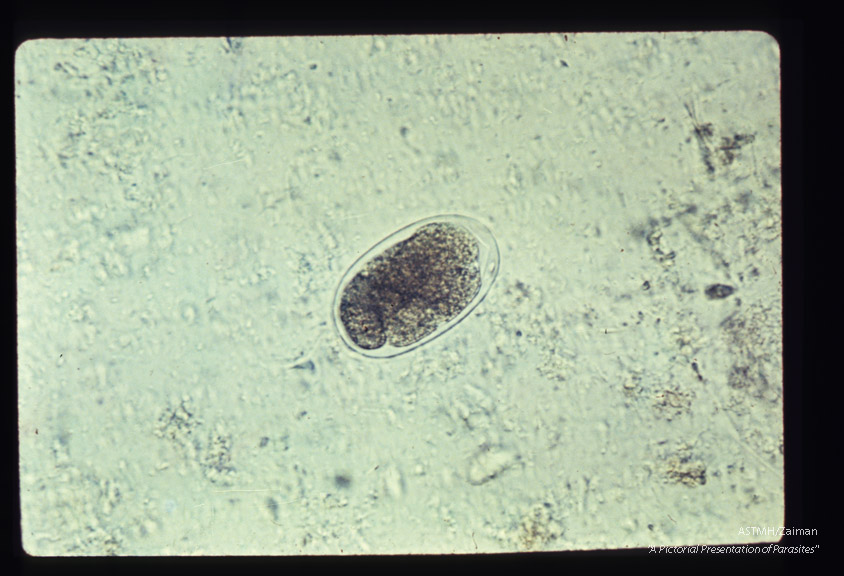

Hookworm eggs